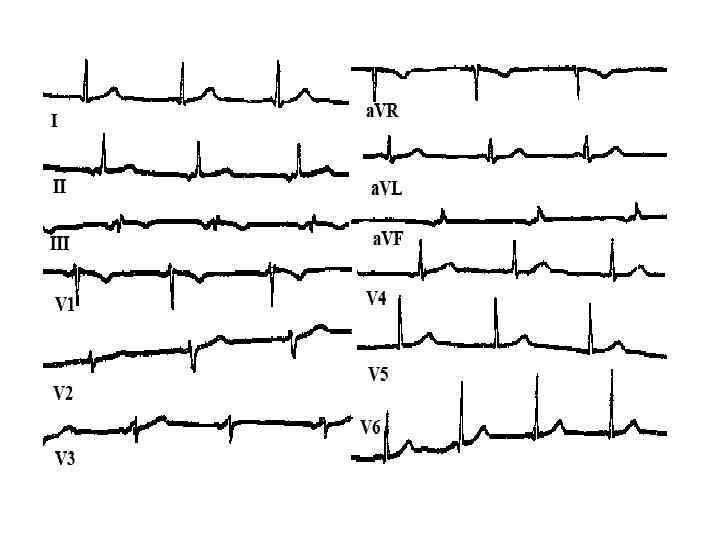

Методы диагностики ЭКГ • нормальная или с неспецифическими изменениями • атриовентрикулярные и внутрижелудочковые блокады • нарушения ритма сердца, МА у 20%

Методы диагностики ЭКГ • нормальная или с неспецифическими изменениями • атриовентрикулярные и внутрижелудочковые блокады • нарушения ритма сердца, МА у 20%

Критерии диагноза АДПЖ III. Нарушения реполяризации Малый Инверсия Т волны в отведениях V 2 и V 3 IV. Нарушения деполяризации/проведения • Большой ü Эпсилон волны или расширение комплекса QRS > 110 мс в отведениях V 1 -V 3 • Малый ü Поздние потенциалы желудочков V. Аритмии Малые ü Желудочковая тахикардия с ЭКГ морфологией БЛНПГ ü Частая желудочковая экстрасистолия > 1000/ 24 часа

Критерии диагноза АДПЖ III. Нарушения реполяризации Малый Инверсия Т волны в отведениях V 2 и V 3 IV. Нарушения деполяризации/проведения • Большой ü Эпсилон волны или расширение комплекса QRS > 110 мс в отведениях V 1 -V 3 • Малый ü Поздние потенциалы желудочков V. Аритмии Малые ü Желудочковая тахикардия с ЭКГ морфологией БЛНПГ ü Частая желудочковая экстрасистолия > 1000/ 24 часа